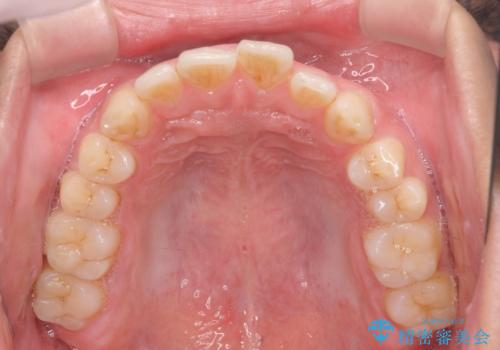

前歯が気になる。インビザラインライト

- 前歯が気になるとの事で来院。

矯正を希望されたが費用と時間を抑えたいとの事でインビザラインライトで矯正を行いました。(奥歯の位置関係はほぼ変えない)

前歯が綺麗に並び大変満足して頂けました。